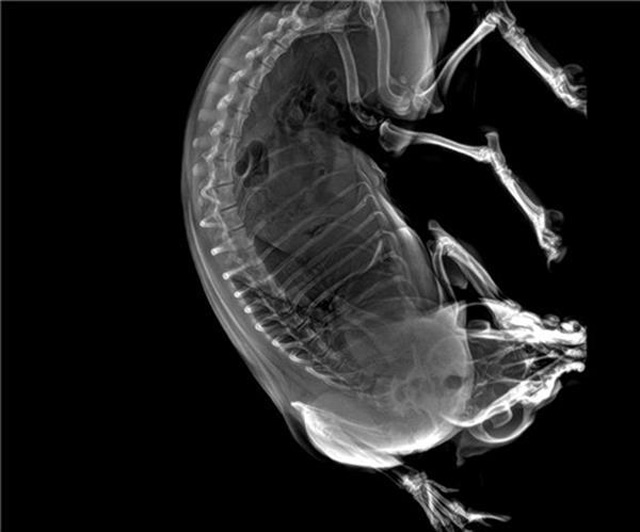

宠物DR的工作原理是X光线穿透动物体后在屏幕或者胶片上面显示体内影像。辅助宠物医生读片跟准确的治疗,宠物DR显示是宠物医院诊所的配置,提高了诊断的效率。DR的检测效率比X线高44%,成像快采集时间10MS以下。3秒左右就可以看到检查图像。常规的胸部DR还要几分钟。所以宠物DR的出片速度是非??斓?。很高的空间分辨率低噪音。可以获得高清图像,提高检测正确率避免误诊等等问题。数字化图像的优势是可以保留原始数据,图片识别,二三维的重建,医学影像学实现全数字化和无胶片化铺平了道路。提供照片打印服务,防止照片丢失而重复照片。有针对性的对图像进行处理,以提高诊断率。宠物DR的辐射量很低的,对人体的辐射风险不大。